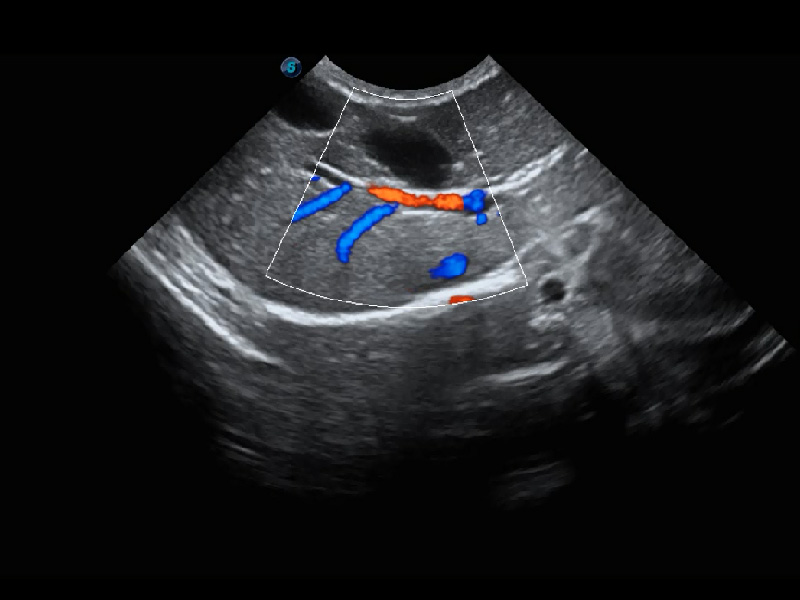

ProPet 60 作为一款高端台式动物超声设备,为动物医生的日常诊断提供了一系列贴合动物临床需求、解决临床实际问题的高级成像功能。凭借全系列高清探头,满足医生对腹部、心脏、生殖、浅表、肌骨等成像的所有需求,切实帮助您提升检查效率,提高诊断信心。

动物是人类最亲密的朋友和最值得信赖的伙伴。新葡的京集团8814检测站也一直致力于探索动物专用的超声影像解决方案。 全新推出的ProPet系列,是新葡的京集团8814检测站在动物超声影像智能化、专业化、精准化的一次跨越式革新。动物不能用言语来表述自己的不适,通过超声影像,ProPet系列搭建了动物医生与不同物种沟通的“桥梁”,为动物医生注入了“治愈之力”。